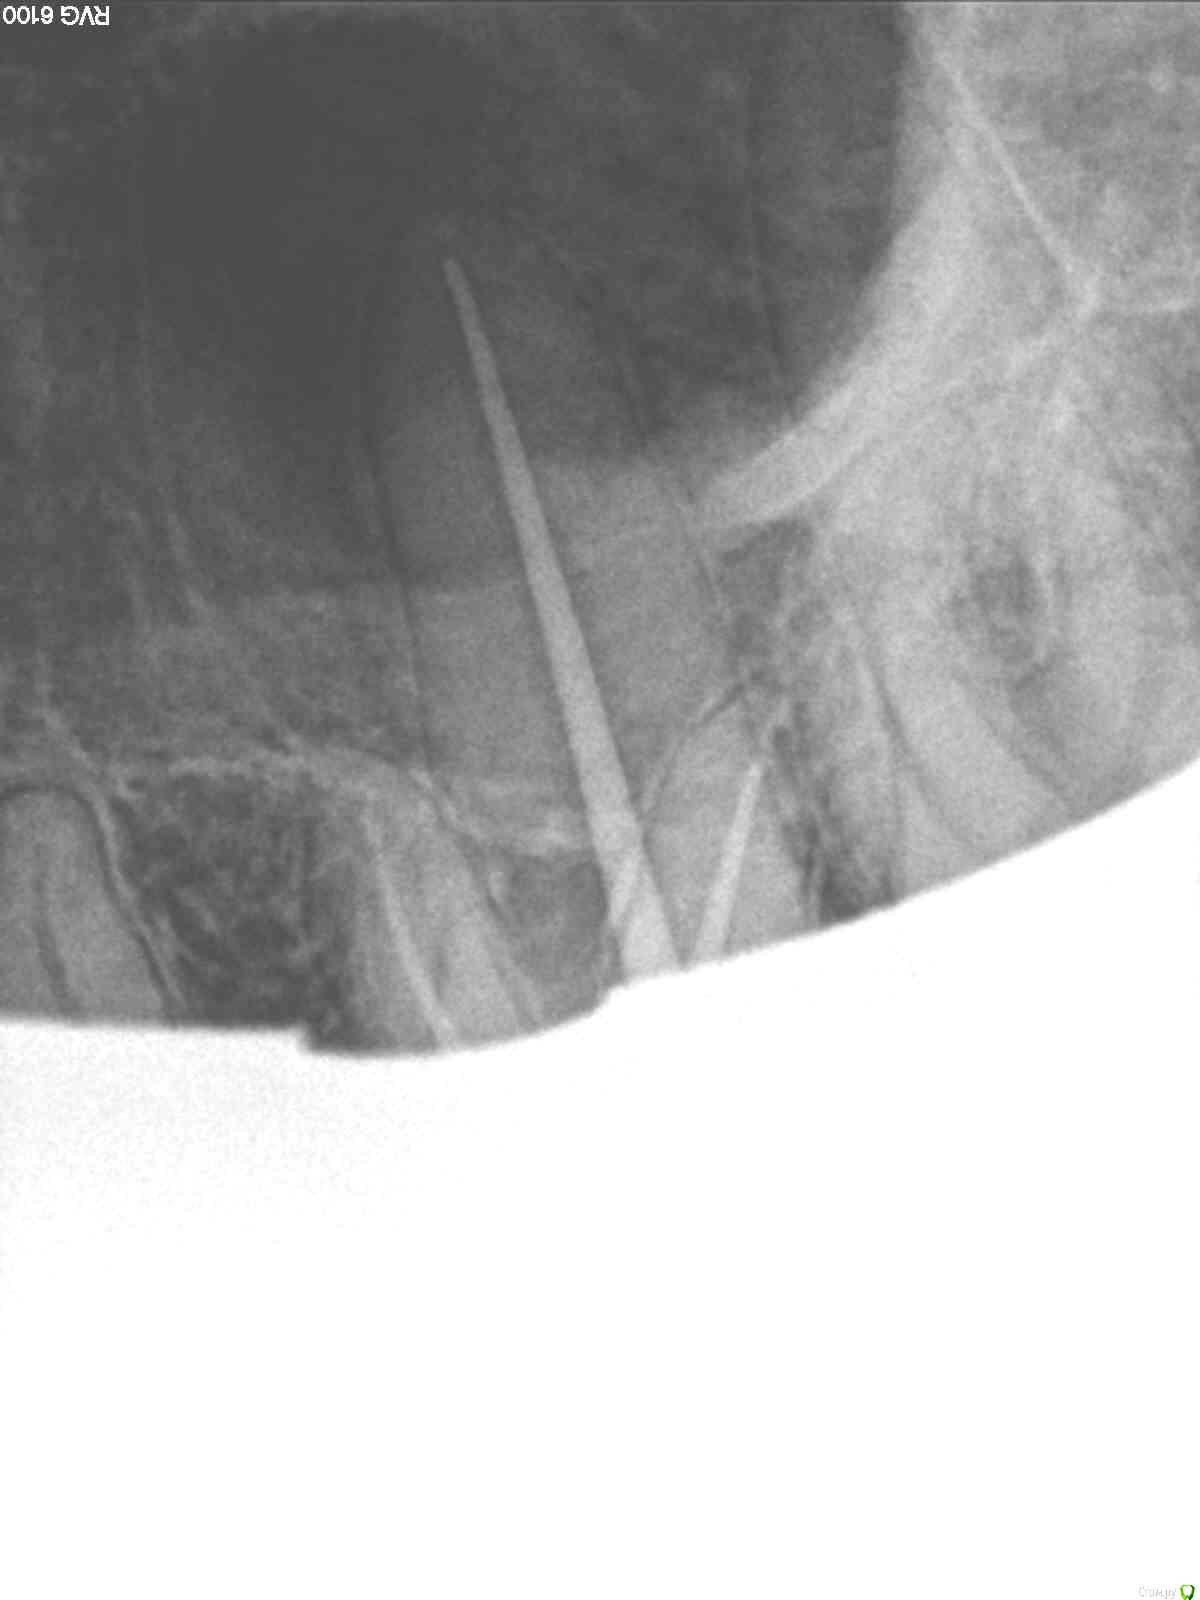

SolnceSamara Опубликовано 24 октября, 2015 Поделиться Опубликовано 24 октября, 2015 почернела старая пломба в давно пролеченной шестерке (сверху). Врач заменила пломбу но зуб болел при надавливании, заменили пломбу повторно-все равно осталась боль, сменила врача-снова сменили пломбу-снова болит, решили депульпировать-снова вынули пломбу, поставили временную-неделю проходила с временной-через неделю окончательно депульпировали, поставили постоянную. Сначало поболело 3 дня, и вроде прошло, хотя остался дискомфорт при надавливании. Прошло 3 недели, боль усилилась, теперь болит не только при надавливании иногда просто звеняще-ноющее ощущение нарастает. Пью нимесил. Посоветуйте что делать-что не так? Снимки прилагаю-делали на протяжении всйх операций (до и после).Разьяснение по снимкам :R1-29/08/15R2,R3-25/09/15R4-R7-28/09/15 Ссылка на комментарий

red_butler Опубликовано 24 октября, 2015 Поделиться Опубликовано 24 октября, 2015 Коллеги поправят, но выглядит как пломбирование одиночным штифтом. Возможно пропущен четвертый канал. Нужна ревизия корневых каналов. 2 Ссылка на комментарий

DmitrySH Опубликовано 24 октября, 2015 Поделиться Опубликовано 24 октября, 2015 Коллеги поправят, но выглядит как пломбирование одиночным штифтом. Возможно пропущен четвертый канал. Нужна ревизия корневых каналов. Все верно. Ссылка на комментарий